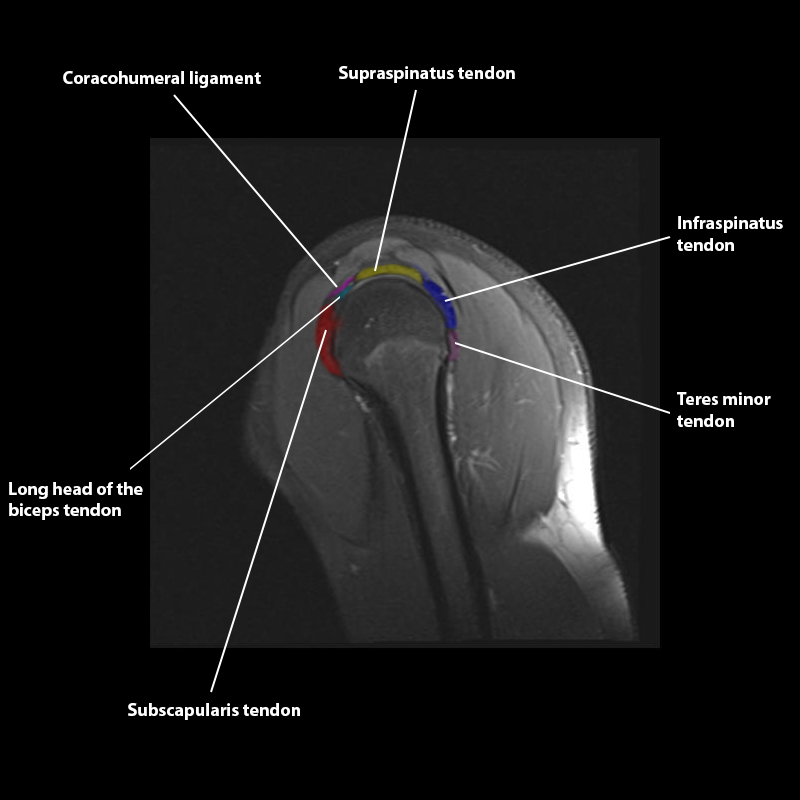

Shoulder MRI Anatomy